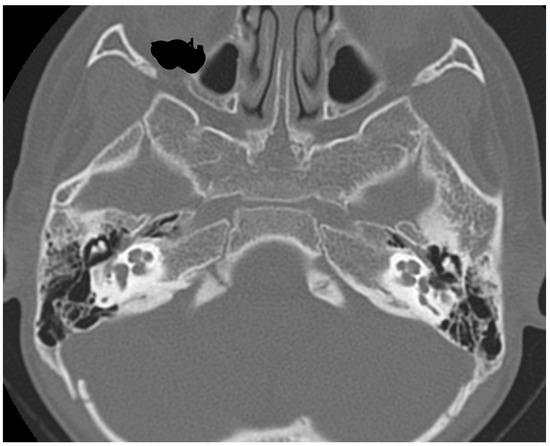

2. Case Report